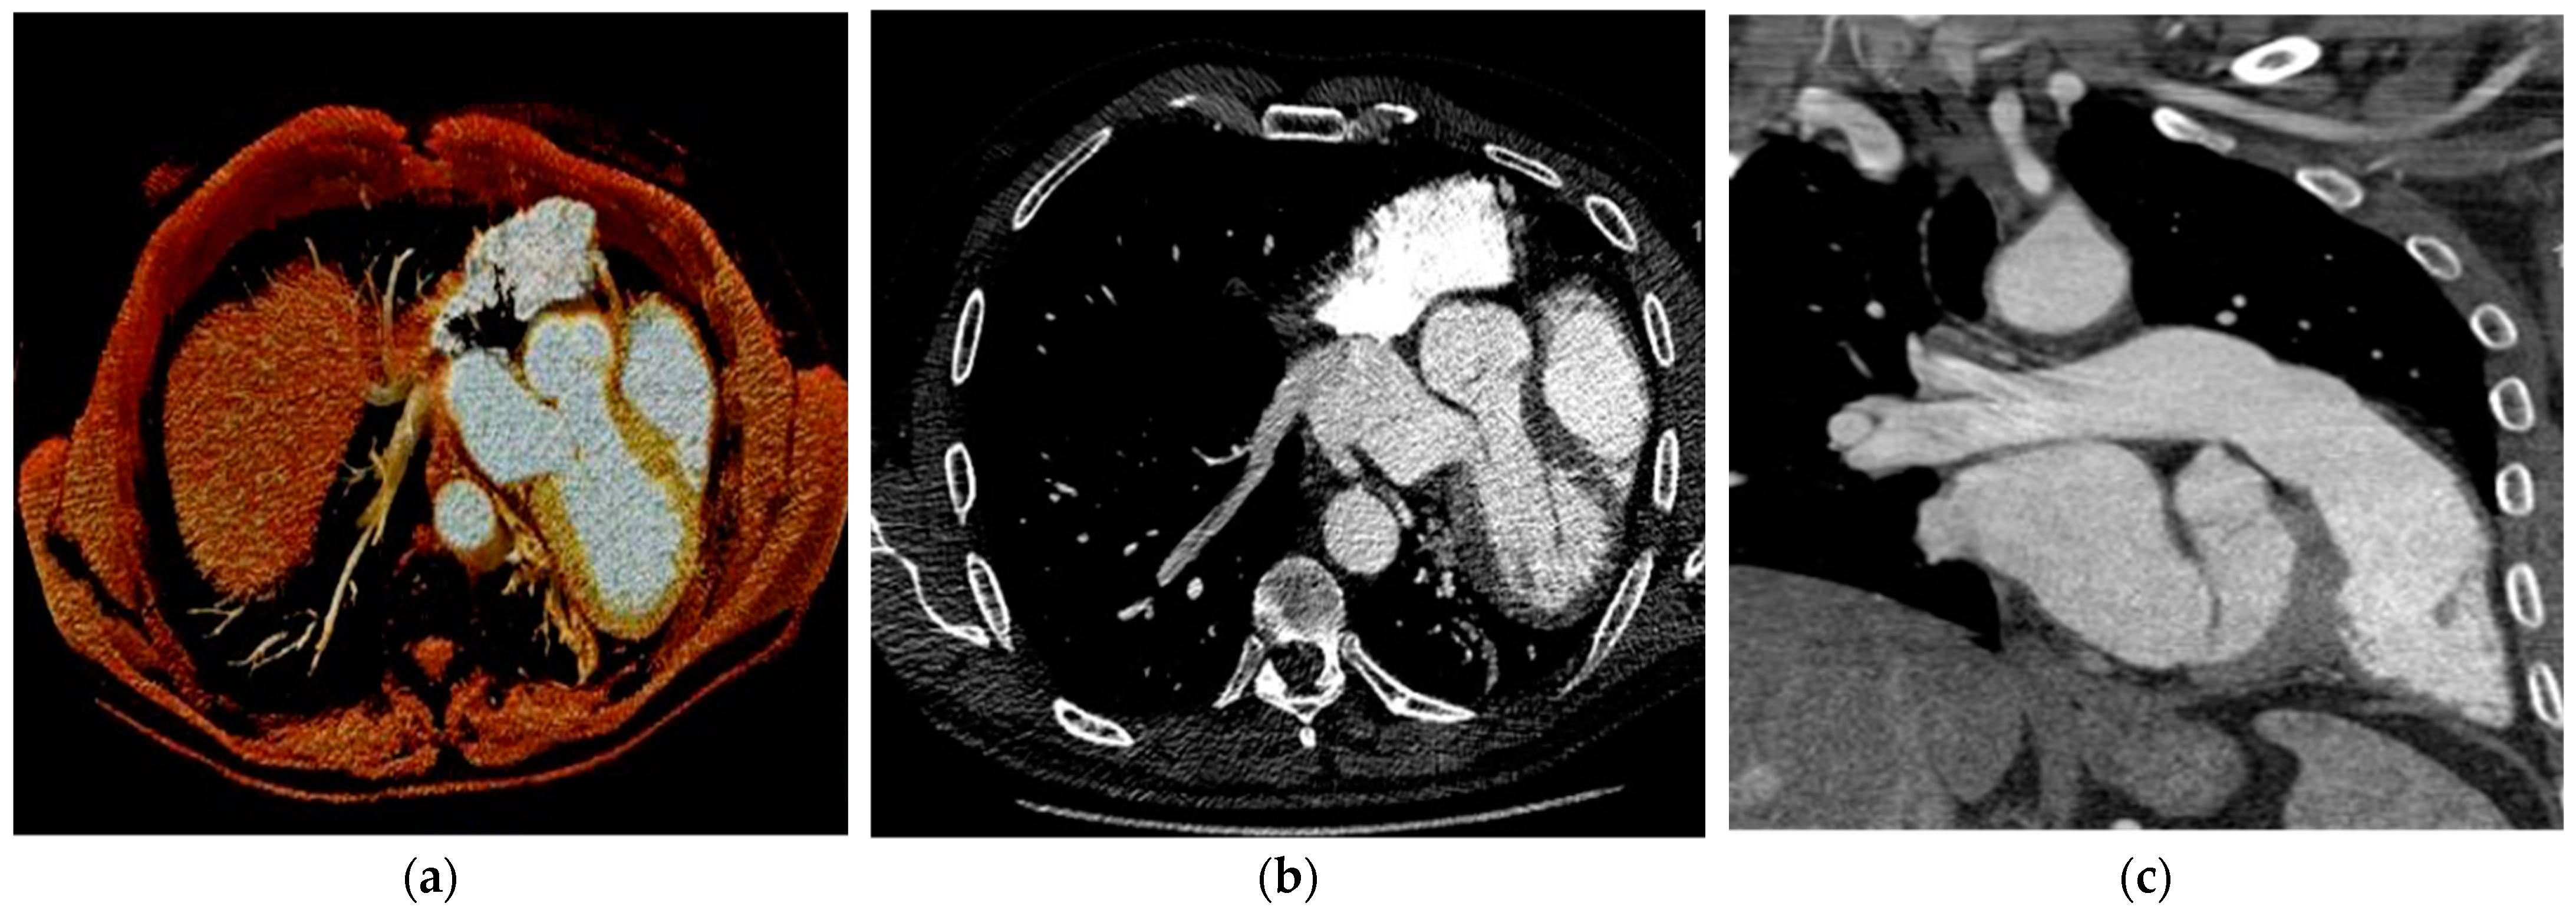

7.4. Cardiac Computed Tomography

| CCT | Evaluation of heart position Evaluation of associated cardiac disease | Spatial resolution Temporal resolution | Radiation dose Low tissue characterization Artifact from metallic implantable devices |